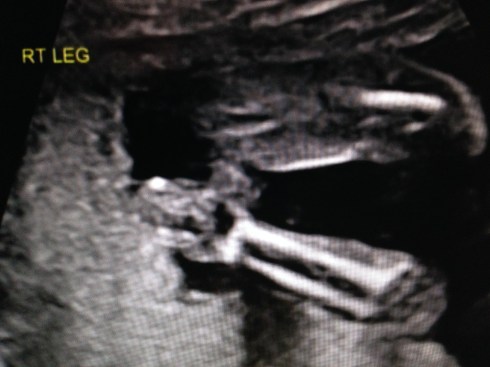

The ultrasound was performed on Friday, March 21, 2014 (at 19 weeks + 4 days). Our boy appeared healthy in all ways and weighed about 10 oz. His growth measurements were between 43% and 62% for his gestational age, and the heart rate was 147 bpm. The placenta is posterior and without previa. My cervix is long. Excellent!

We received a DVD of the scan. I took this short video clip with my phone, that shows baby’s face: moving his jaw, yawning, moving his tongue, and even smiling. You can also see his forearm in front of his face. Watch it again and look for the heart beating. Precious!!

I took these images by pausing the DVD and taking screen shots: